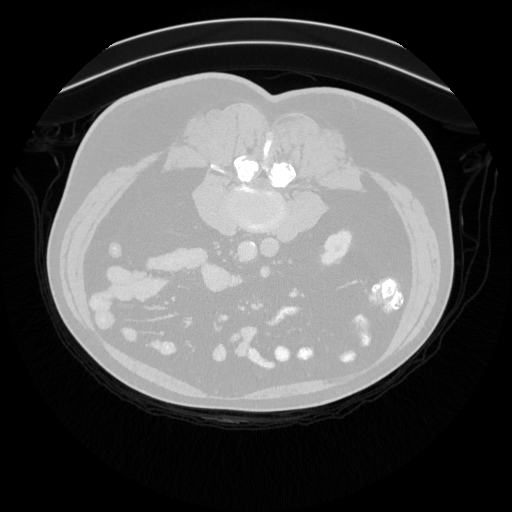

Figure 1: Example of moving (top) and fixed (bottom) image pairs. From left to right: brain MRI (T2w, T1w, T1Gd), abdomen CT from different subjects, retinal OCTA choroid, and retinal OCTA SCP scans

To address this problem, we propose a meta-learning-based registration meth-od that can efficiently use data from different domains. Specifically, we integrate an unsupervised learning-based registration model in a gradient-based meta-learning framework. The registration model is first trained using multiple registration datasets and then performs task-level learning using the multi-task data. The meta-learner finds an initialization point which can quickly adapt to various registration problems. After that, fine tuning is performed with the data of the target domain and applied to the test set. To demonstrate superiority, we trained the model for various 2D registration tasks from retinal Optical Coherence Tomography Angiography (OCTA) choroid, abdomen CT, and brain MRI scans and tested it on a registration of retinal OCTA Superficial Capillary Plexus (SCP) scans as shown in Fig. 1.

In our experiment, we used four datasets including retinal OCTA SCP, retinal OCTA choroid, abdomen CT, and Brain MRI. Both OCTA SCP and choroid datasets contained 368 moving and fixed image pairs collected from local university hospital, some of which were taken from same subjects at different times. The abdomen CT and brain MRI images were obtained from public Decathlon dataset [15]. Here, we define three tasks according to modality (T1w, T1Gd, and T2w) from the brain MRI dataset and two tasks in the abdomen CT dataset. Each 3D volume was divided in multiple axial slices and adjacent two slices were defined as a (M,F)𝑀𝐹(M,F) pair. All images were resized to a size of 400×400400400400\times 400 and histogram equalization was applied. Also, the range of intensity was rescaled to [0,1]. For training, we defined a set of five tasks as the source task set Tsource=subscript𝑇𝑠𝑜𝑢𝑟𝑐𝑒absentT_{source}= TbrainT1subscript𝑇𝑏𝑟𝑎𝑖𝑛𝑇1T_{brainT1}, TbrainT1Gdsubscript𝑇𝑏𝑟𝑎𝑖𝑛𝑇1𝐺𝑑T_{brainT1Gd}, TbrainT2subscript𝑇𝑏𝑟𝑎𝑖𝑛𝑇2T_{brainT2}, Tabdomensubscript𝑇𝑎𝑏𝑑𝑜𝑚𝑒𝑛T_{abdomen}, TChoroidsubscript𝑇𝐶𝑜𝑟𝑜𝑖𝑑T_{Choroid}. For evaluation, retinal OCTA SCP dataset was used as target domain data Dtargetsubscript𝐷𝑡𝑎𝑟𝑔𝑒𝑡D_{target}. It was divided into a fine-tuning set Tfinetunesubscript𝑇𝑓𝑖𝑛𝑒𝑡𝑢𝑛𝑒T_{fine-tune} (294 pairs) and a test set Ttestsubscript𝑇𝑡𝑒𝑠𝑡T_{test} (74 pairs). For evaluation, we manually labeled 20similar-to\sim30 bifurcation points on image pairs in Ttestsubscript𝑇𝑡𝑒𝑠𝑡T_{test}.